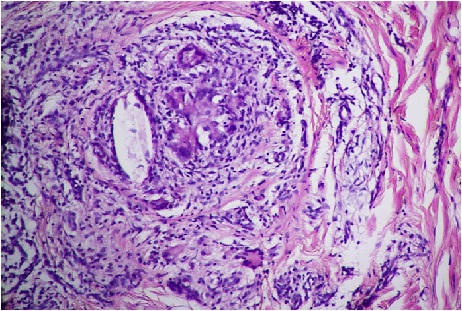

Histopathological examination of sinus tract biopsy showed granulomas in deep dermis, with Langhans giant cells, epitheliod cells and histiocytes, which were suggestive of scrofuloderma, as has been shown in [Table/Fig-4,5].

Microscopic view showing the typical granuloma formation